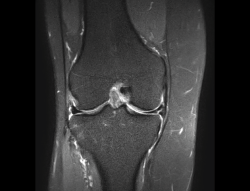

1.2. Ligamentos

Se visualizan como estructuras lineales hipointensas en todas las secuencias.

1.2.1. Ligamentos laterales

Figura 36. Corte de secuencia coronal T2 Fat-Sat: ligamentos colaterales normales.

Ligamento lateral interno (LLI) y ligamento lateral externo (LLE) (Figuras 36, 37, 38 y 39).

Figura 37. Corte de secuencia coronal T2 Fat-Sat de rodilla: pequeño edema en el LLI, banda medial por esguince del LLI de grado I.

Figura 38. Corte de secuencia coronal T2 Fat-Sat de resonancia magnética de rodilla: edema y pequeña rotura de fibras mediales del ligamento lateral interno (LLI). Esguince del LLI de grado II.

Figura 39. Corte de secuencia coronal T2 Fat-Sat de resonancia magnética de rodilla: edema y rotura del ligamento lateral externo de su inserción peroneal con retracción ligamentosa. Esguince de grado III.